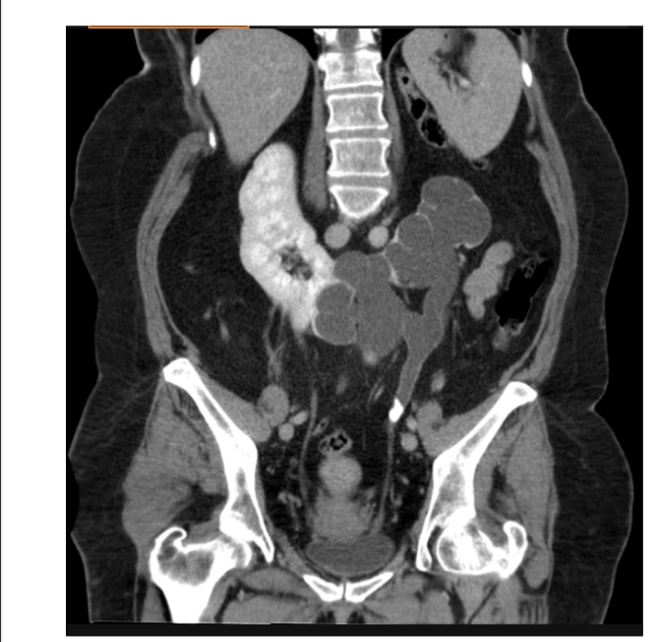

What is the CT + Pathology?

Abdomen CT C+

- In arterial phase as the abdominal

aorta has maximum opacification • Path = renal cell carcinoma

- Heterogenous mass on the kidney

with poorly defined margins